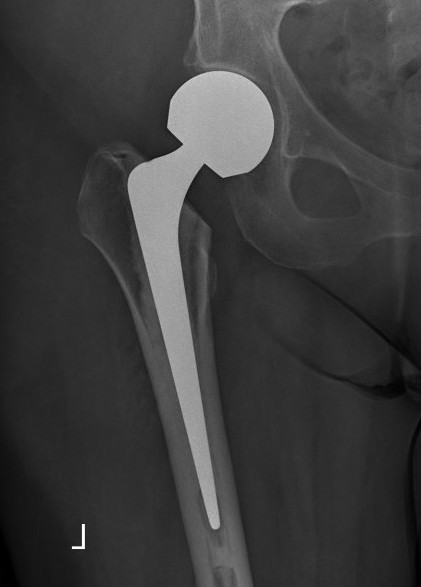

Bipolar modular

Concept

- second articulation between inner smaller head and polyethylene liner

- reduce wears on acetabulum

- improved function and less pain

- may reduce dislocation

- may have better ROM

Issues

- higher cost

- may need open reduction in dislocation if femoral head disassociates from socket

- loss of motion interface / becomes unipolar